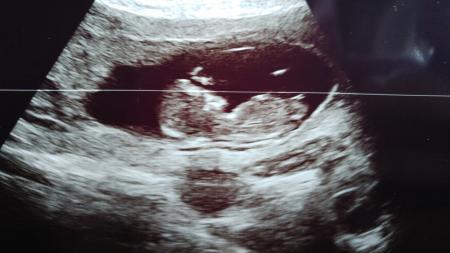

Ich bin wieder da. Mit unserem Zwerg ist alles ok und ich wurde 5 Tage vordatiert. Bzgl des Hämatoms hat mein Arzt sich leider nicht wirklich geäußert..alles in allem bin ich sehr enttäuscht von meinem Doc...berichte gleich noch ausführlich.

Hallo meine liebe :) Erst mal vorweg: schön dass es dir und deinem krümli gut geht!!!! Und das Bild ist wirklich sehr schön Und warum dein arzt so fahrlässig ist kann ich echt nicht verstehen. Besteht für dich noch die Möglichkeit de Arzt komplett zu wechseln? Das kann ja so nicht die ganze SS weiter gehen